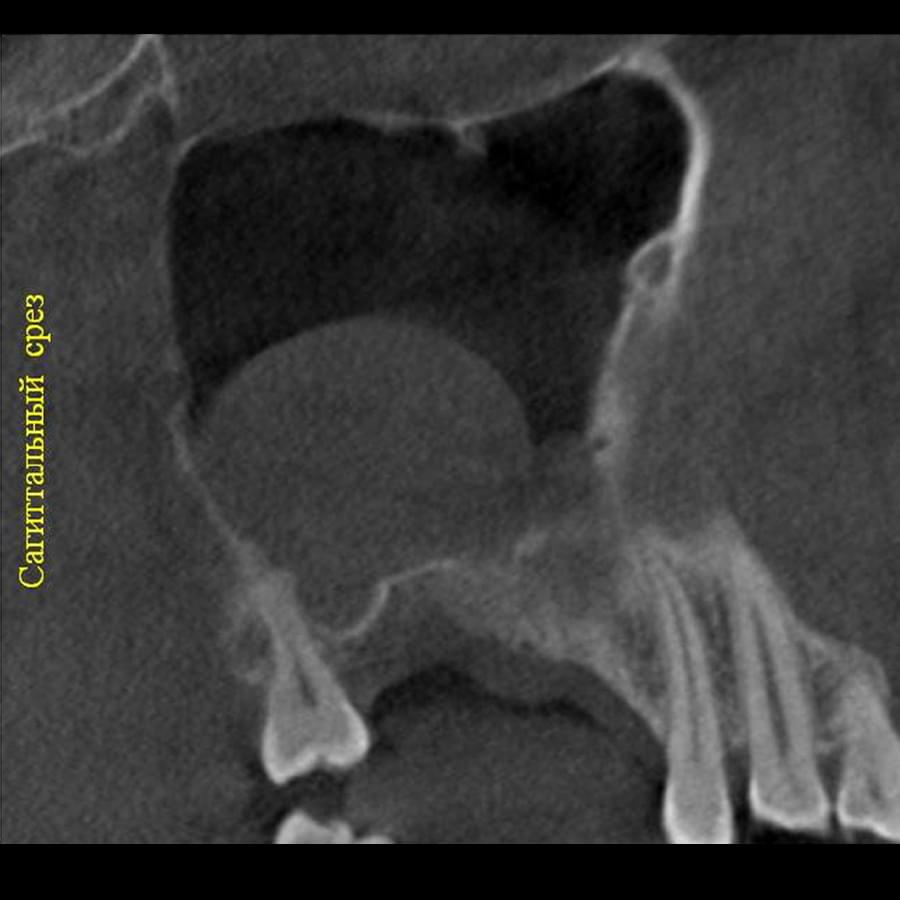

Отримайте вичерпну інформацію про стан ЛОР-органів завдяки надточній діагностиці на апараті

PLANMECA. Наші знімки дозволяють детально візуалізувати всі групи навколоносових синусів,

структури остіомеатального комплексу та анатомію носової перегородки.

Ми надаємо не просто знімок, а повний діагностичний сервіс:

Детальний опис: Кожне дослідження супроводжується професійним висновком лікаря-рентгенолога

з описом виявлених патологій (кісти, поліпи, сторонні тіла, рівень рідини, потовщення

слизової).

Зручна візуалізація: Можливість перегляду структур у будь-якій проекції (аксіальній,

корональній, сагітальній) для точної локалізації запального процесу.